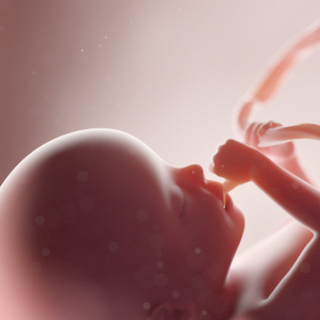

تطور وجه الجنين خلال الحمل في الشهر الثاني

تستمر ملامح وجه الجنين بالتكون خلال الحمل في الشهر الثاني، فتظهر الأذنان على شكل طيتان صغيرتان على الرأس، وتبدأ العيون والأنف بالتكون، مع بدء تكون القدرة على الشم.

تطور الجسم الخارجي للجنين خلال الحمل في الشهر الثاني

تنمو الأطراف في الشهر الثاني من الحمل مكونةً الذراعين والساقين، وتظهر الأصابع بشكل مكفف، ويكتمل نمو الأنبوب العصبي خلال الشهر الثاني.

حركة الجنين خلال الحمل في الشهر الثاني

بالرغم من عدم شعور الحامل بالجنين، إلا أن الجنين يبدأ بالتحرك والركل باستخدام أطرافه حديثة النمو في الشهر الثاني.

طول ووزن الجنين في نهاية الشهر الثاني من الحمل

يصل طول الجنين مع نهاية الشهر الثاني من الحمل إلى ما يقارب 2.54 سنتمتر، ويزن تقريبًا 9.45 غرام.